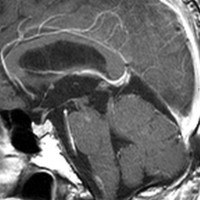

脳血管撮影の静脈層です。 血管腫の内側に刷毛で掃いたような異常な静脈が見えます。これは静脈性血管腫といって,大きな海綿状血管腫にはよく合併する異常です。海綿状血管腫をとるときに誤ってこの静脈性血管腫を傷つけてしまうと,静脈梗塞が起きるので注意しなければなりません。このケースの場合はもし損傷すると左側頭葉内側の脳損傷になります。